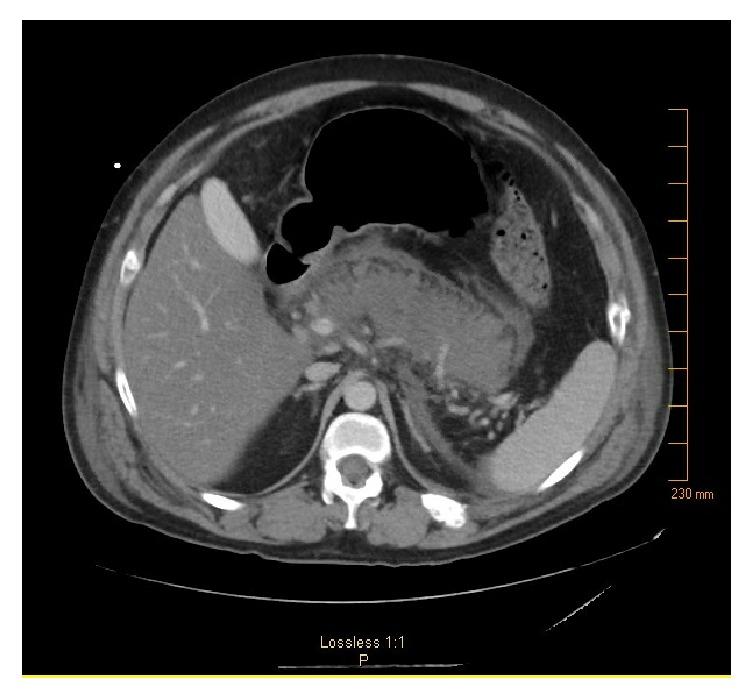

Initiation of insulin therapy can be challenging for patients; proper training should be given by physicians and certified educators to ensure correct and safe use for outpatient population. Different insulin strengths are now available in the US; while U-40 insulin does not exist in the United States for humans, it is a very common strength used in animals. We are reporting a 30-year-old male that became insulin dependent after hospitalization for necrotizing pancreatitis who was using U-40 syringes to draw from the prescribed insulin U-100 and also presented with repeated hypoglycemic episodes.

启动胰岛素治疗对患者来说可能具有挑战性;医生和经过认证的教育工作者应提供适当培训,以确保门诊患者正确、安全地使用胰岛素。目前美国有不同强度的胰岛素;虽然美国已不再生产用于人类的U - 40胰岛素,但它是动物常用的一种强度。我们报告了一名30岁男性,他因坏死性胰腺炎住院后开始依赖胰岛素治疗,使用U - 40注射器抽取处方的U - 100胰岛素,并且反复出现低血糖发作。